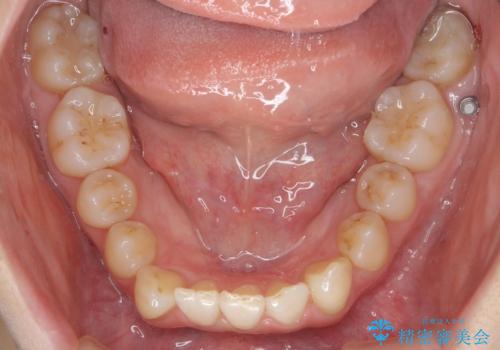

- 前歯のがたつきを主訴に来院。

下の前歯は生まれつき1本少ない状態でした。

左上の犬歯が入りきらずねじれており、かみ合わせもずれていました。

左上の小臼歯を1本抜いて治療しています。

前歯は内側に傾いており(ラビッティング)、過蓋咬合(深いかみ合わせ)を呈していました。

難しい治療でしたが綺麗に咬み合わせることができ、また前歯もしっかり当たるように治療できました。